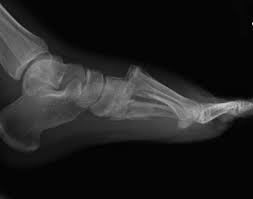

Radiologists must have a thorough understanding of anatomy, mechanisms, and patterns of these injuries to diagnose and help. A lisfranc injury, also known as a lisfranc fracture, happens when bones break or ligaments tear in the region in the middle of the feet. A lisfranc injury occurs when one or more of the metatarsal bones are displaced from the tarsus, which is a cluster of bones at the top of the foot, just below the ankle joint. However, most athletes are able to successfully. Stable lisfranc injuries that do not require surgery may cause an athlete to miss 2 months or more of their season. Lisfranc injuries are a spectrum of injuries to the tarsometatarsal joint complex of the midfoot. Lisfranc injury or midfoot injury that result if bones in the midfoot are broken or ligaments that support the midfoot are torn. • medial edge of 2nd mt base should line up with the medial edge of middle cuneiform. A lisfranc injury or lisfranc sprain is an injury to the ligaments in the middle part of the foot, called the midfoot. Lisfranc injury indicates disruption between. Recovery can be slow and painful. It can occur in one or both feet. Ebraheim's animated educational video describing lisfranc injury.